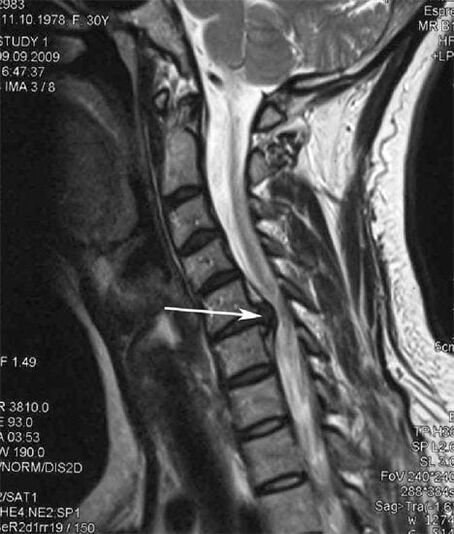

Aux premiers stades, l'ostéochondrose est détectée par IRM. Par la suite, la pathologie peut être diagnostiquée par radiographie. Sur les radiographies de la colonne cervicale, une diminution de la distance entre les vertèbres, des modifications pathologiques des facettes articulaires et une ostéophytose deviennent évidentes.

De nombreuses personnes se plaignent de ne pas pouvoir tourner le cou en raison de la douleur intense qui apparaît après avoir soudainement soulevé quelque chose de lourd. Ce phénomène indique la formation d'une hernie discale. La cause des douleurs dans le dos, le cou et les membres supérieurs est le pincement de l'une des racines nerveuses émergeant de la moelle épinière.